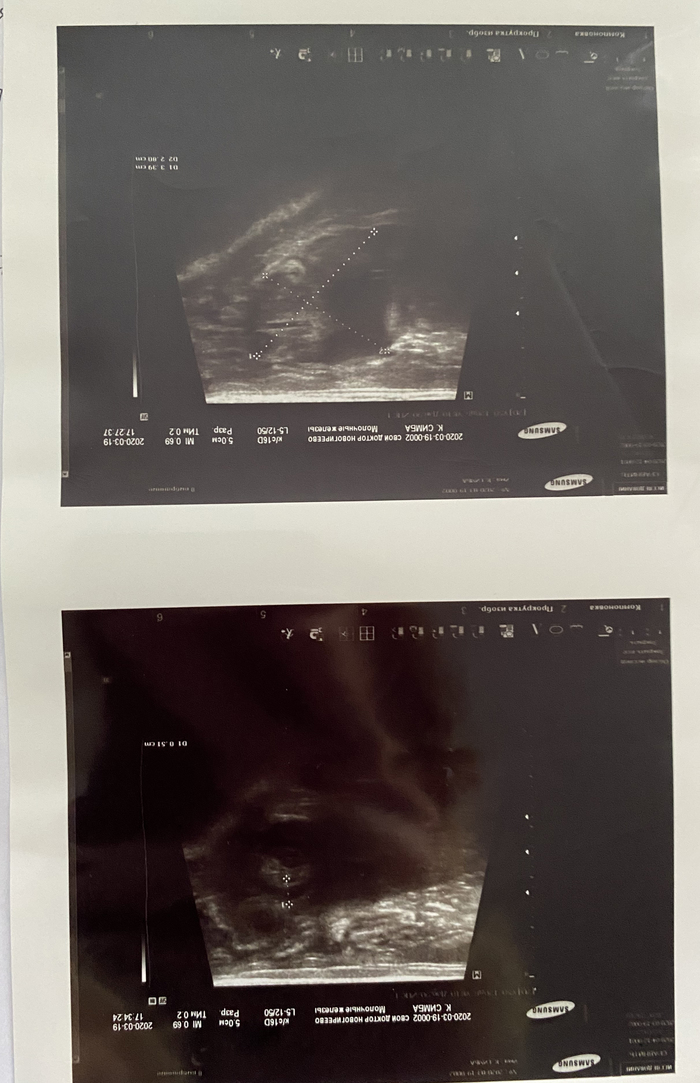

После этого кот стал вялый, много лежал и у него начался понос. Понесли в клинику на приём. Сделали узи, у него в животе была свободная жидкость. Очень надеялись, что на препаратах будет лучше и обойдётся, но на крайнем узи нашли новообразование и решили делать лапаротомию. Коту становилось хуже на глазах. Сделали операцию, сдали ещё раз кровь и нашли в плюс к багажу Коронавирус, который перерос молниеносно в - Коронавирусный энтерит. Коту вырезали лимфоузел и часть кишечника для биопсии. Мы уже знали, что он обречён, но придерживались всех рекомендаций. После гистологии поставили диагноз, который втоптал окончательно в пол всех нас - «лимфома».

Я не буду выкладывать всю гору бумаг и назначений. Прикрепляю основные бумаги с перечисленными диагнозами, проведением операции и узи.